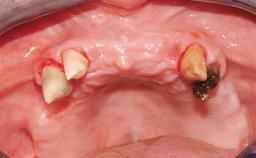

Immediate Implant Placement and Immediate Provisionalization with a Prefabricated-Shell Provisional Crown

In this case, Arndt Happe describes how he achieved a stable outcome at 5 years by giving careful attention to the coronal aspect of the transmucosal area of the provisional, creating a slim emergence profile.

A healthy 31-year-old female patient presented with a failing maxillary left lateral incisor crown. The crown regularly loosened, and the remaining tooth was neither restorable nor rational to treat. The patient had a high smile line, a medium soft tissue biotype with a compromised mesial papilla (shorter than the contralateral one), and a horizontal scar in the buccal soft tissue as a result of past periapical surgery.